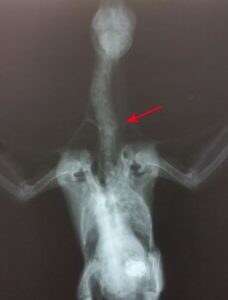

This fledgling baby pigeon was rescued last month by two pedestrians who found her injured on a sidewalk in Oakland, California. Seeing her twisted neck, they weren’t sure at first if she was even alive – until she began to peep.

“We weren’t sure if she was going to make it,” said Piazza. “She was a long shot. Any living being with a broken neck is in trouble. But with the fact that she could still use her legs and her wings, we thought she had a chance. Her spinal cord wasn’t severed, so we thought we’d try to help her.”

Four days later, while refitting the neck brace, it was discovered that the bird was now able to hold her head up nearly all the way.